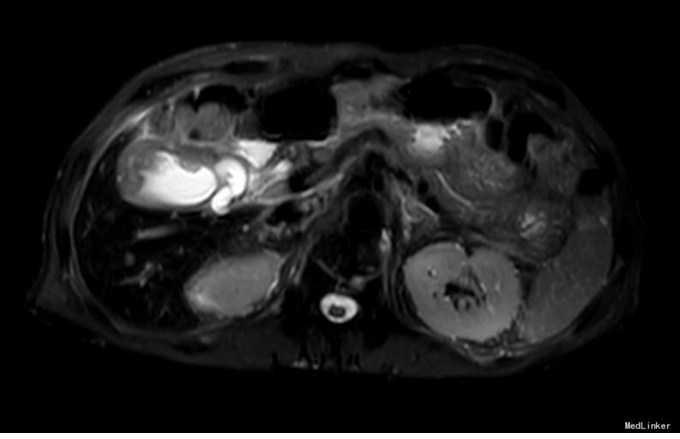

查体:右上腹轻压痛,无反跳痛、肌紧张。墨菲氏征弱阳性。 辅助检查:腹部CT:胆囊体积增大,壁增厚,以胆囊底部为著,增强扫描可见轻度强化,胆囊周围可见积液。MRI:胆囊增大,壁增厚,壁内可见多发结节状低信号灶。胆囊内可见泥沙样短T2信号影。